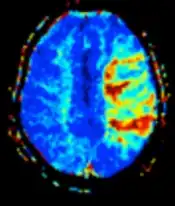

| Diffusion weighted (DWI) | Conventional | DWI | Measure of Brownian motion of water molecules.[80] | High signal within minutes of cerebral infarction (pictured).[81] |

|

| Perfusion weighted (PWI) | Dynamic susceptibility contrast | DSC | Measures changes over time in susceptibility-induced signal loss due to gadolinium contrast injection.[86] |